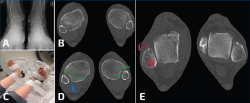

Por otro lado, conocemos que existen otras secuelas, como complicaciones de los esguinces de tobillo. En ocasiones, pasa desapercibido el llamado “esguince alto”, cuyos síntomas alrededor de la sindesmosis pueden producir consecuencias degenerativas, al variar el pico de presiones sobre las superficies articulares implicadas en el tobillo. Mediante una carga axial y rotación externa mantenida con el uso de este dispositivo de carga simulada y, tras unos cortes axiales de TC comparados de ambos tobillos, es posible medir las variables de rotación del peroné, así como una traslación posterior en el plano sagital, evidenciando una inestabilidad de la articulación tibioperonea distal. No en pocas ocasiones esta lesión viene asociada a la rotura del ligamento peroneoastragalino anterior (PAA), por lo que su reparación aislada podría estar abocada al fracaso (Figura 7).

Figura 7. A: radiografías en carga de un paciente con inestabilidad crónica del tobillo derecho; B: tomografía computarizada (TC) en descarga bilateral del mismo paciente; C: imagen de la posición durante la TC dinámica en carga simulada, eversión y rotación externa forzada; D: nótese la inestabilidad de la articulación tibioperonea distal durante la carga (flecha azul); E: relación entre peroné y astrágalo en este paciente con inestabilidad de tobillo y afectación de la articulación tibioperonea. Nótese la posición posterior del peroné y la rotación externa (flecha roja).